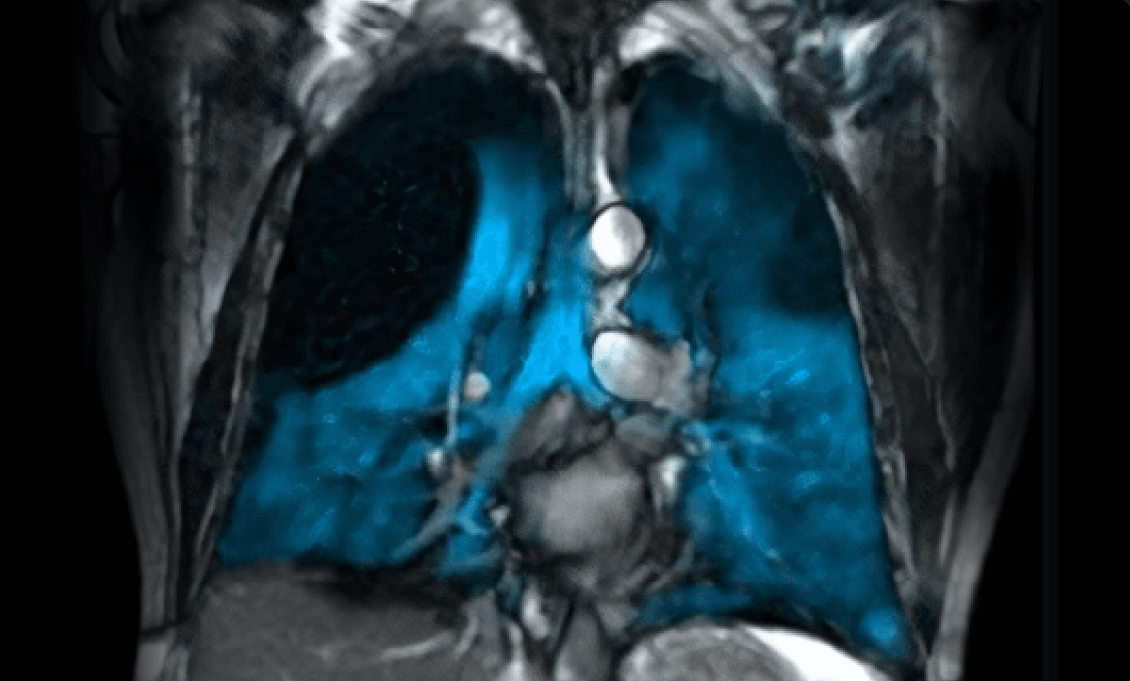

The UAB Center for Lung Analytics and Imaging Research (CLAIR), in collaboration with the Research MRI Core (RMRIC), has successfully performed the first Xenon-129 MRI lung imaging at UAB.

Xenon MRI uses hyperpolarized xenon gas to create detailed functional images of lung ventilation without ionizing radiation, making it safe for both adults and children. The technology, implemented using state-of-the-art hyperpolarizer system, enables visualization of ventilation defects and gas exchange abnormalities invisible to conventional imaging. This opens unprecedented opportunities for early disease detection, treatment monitoring, and research into conditions including COPD, asthma, cystic fibrosis, and post-COVID lung complications.